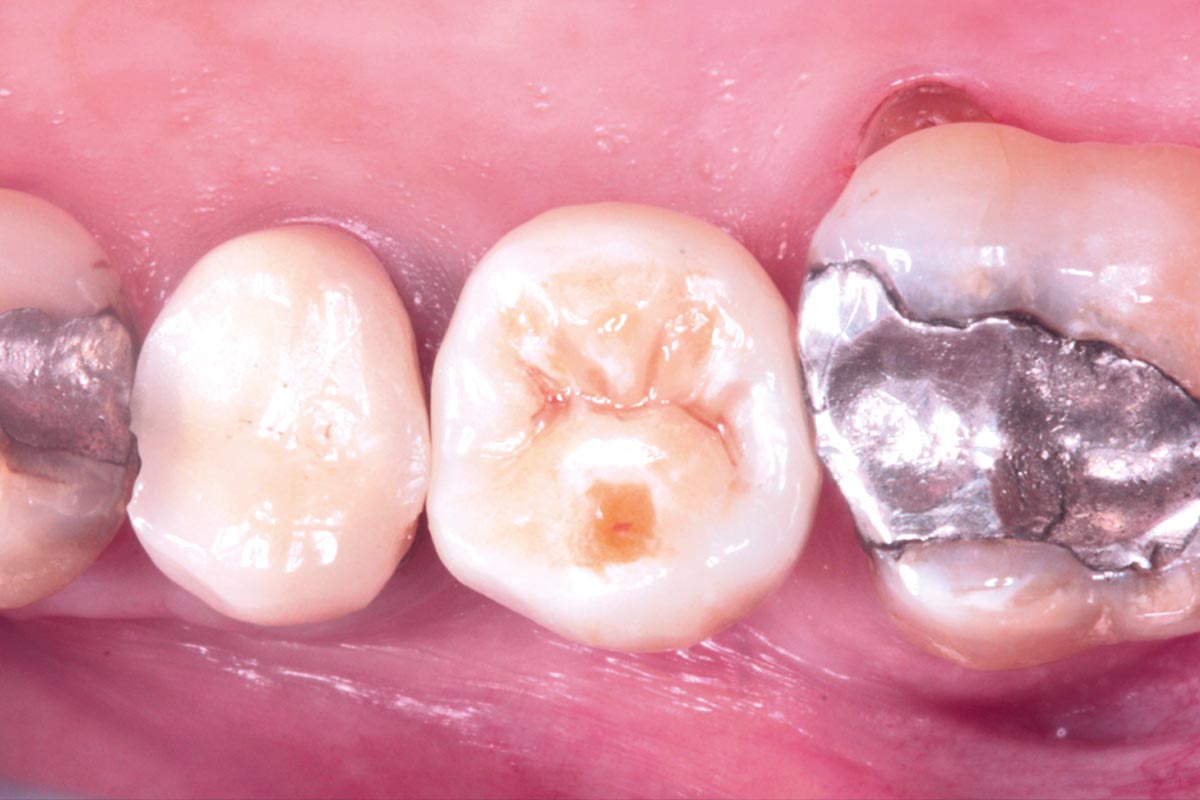

Initial clinical situation. Atrophic maxillary ridge.